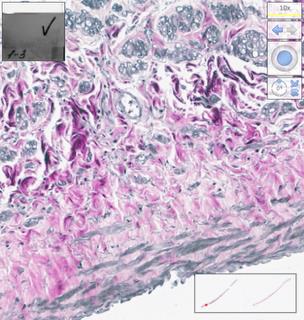

Portions of the muscle wall with areas of nuclei alterations in the form of fragmentation and lysis were identified (Figure 4). The obtained results are demonstrated by slides of histological preparations in a limited but representative assortment (Figures 5–16).

Fig. 4. Fragmentation and lysis of smooth myocyte nuclei in a homograph. Indicated by an arrow (magnified × 400).